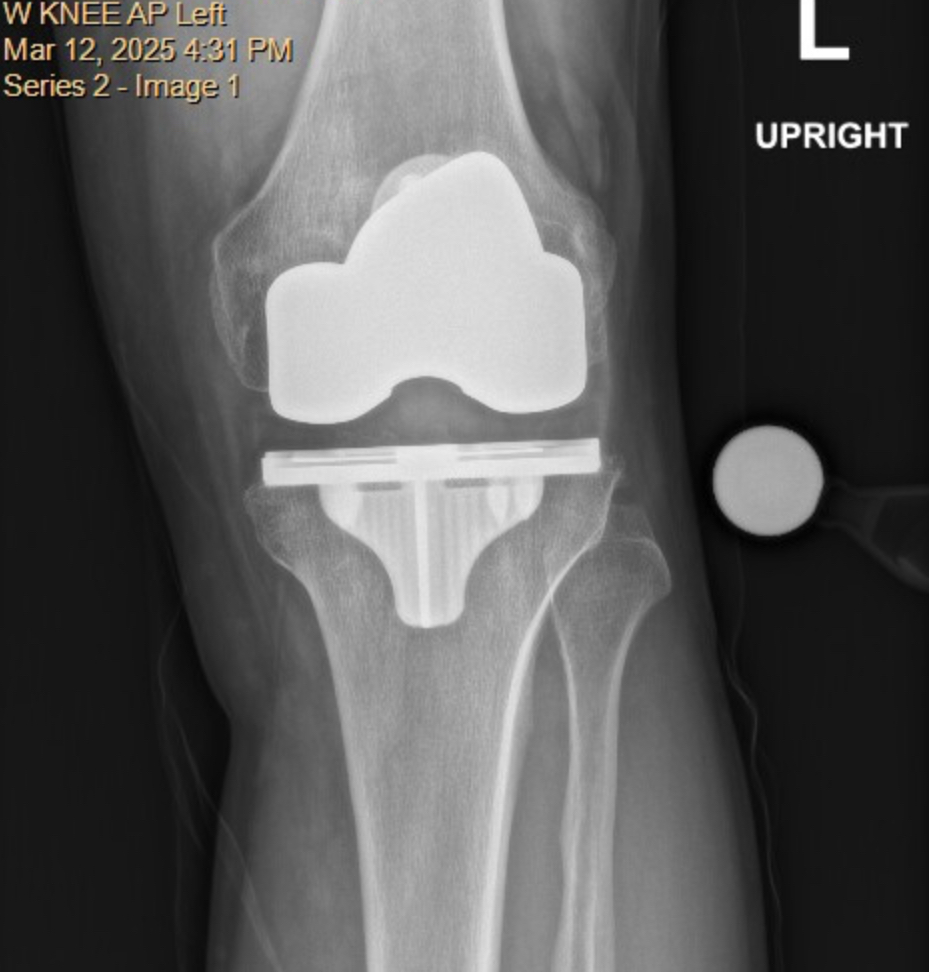

Left TKA Revision

Had the original TKA in Dec2020, never really got any relief. 4 1/2 years of living with and finally decided to see what can be done. Met with an ortho at Yale how specializes in revisions. Originally her plan was to just replace the plastic bearing surface on top of the tibial component with a thicker piece to try and stabilize the joint.

At the 4 week pre-op we both independently came to the conclusion that maybe it would be better to replace everything and start fresh.

Bit of a difference in hardware in the before and after x-rays:

After: